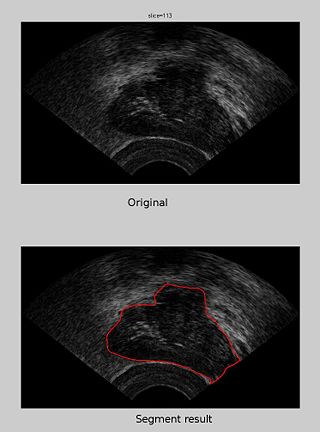

The segmentation of one slice of the ultrasound prostate images

In this work, we develop tools for the segmentation of the prostate from MRI and ultrasound imagery.

Our approach includes grow cut and spherical wavelet based segmentation tools. We will build a command-line tool using ITK which will then be integrated into Slicer3.